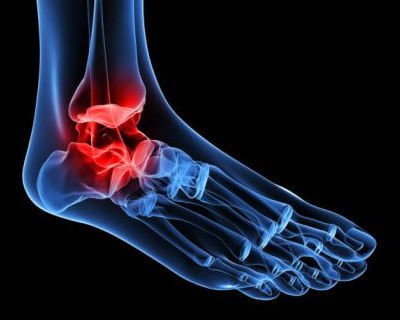

Esse tipo de artrose se origina pelo desgaste progressivo da cartilagem das articulações do tornozelo. É comum que, com o passar dos anos, o tornozelo se mostre mais rígido e com deformações.

Também podem aparecer os clássicos esporões ósseos que é uma condição muito dolorosa, além de limitante.